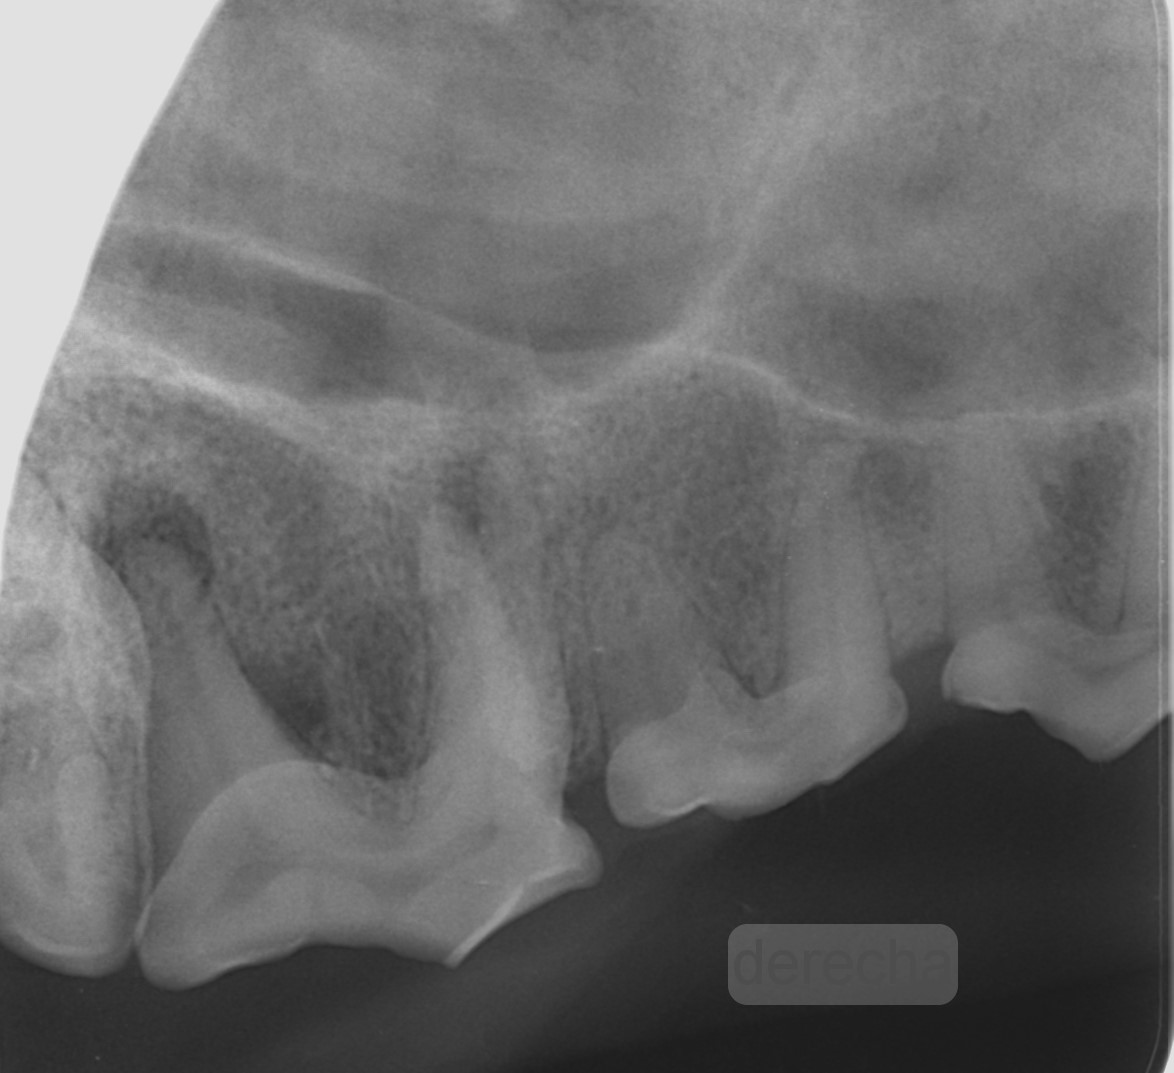

Uno de los aspectos importantes de la radiología es reconocer las estructuras del diente para detectar sus posibles alteraciones. En la imagen 1 se muestra una radiografía intraoral de un primer molar mandibular derecho (409) sano que nos permite ilustrar e identificar su aspecto radiológico. Así, el esmalte, la dentina y el hueso alveolar son radiopacas y la cámara y canal pulpar, así como el espacio del ligamento periodontal, son radiolúcidas.

Dentro de las estructuras anatómicas también podemos evaluar la maduración del canal pulpar, ya que este disminuye gradualmente con la edad por la formación continua de dentina secundaria. Así, por ejemplo, en el gato a los 6 meses su tamaño es de 0,56 mm, a los 12 meses de 0,27 mm, a los 32 meses de 0,18 mm y a los 5 años de 0,15 mm (Kyoungsun, 2014). Esto nos permite aproximarnos a la edad del paciente, como hemos mencionado anteriormente.